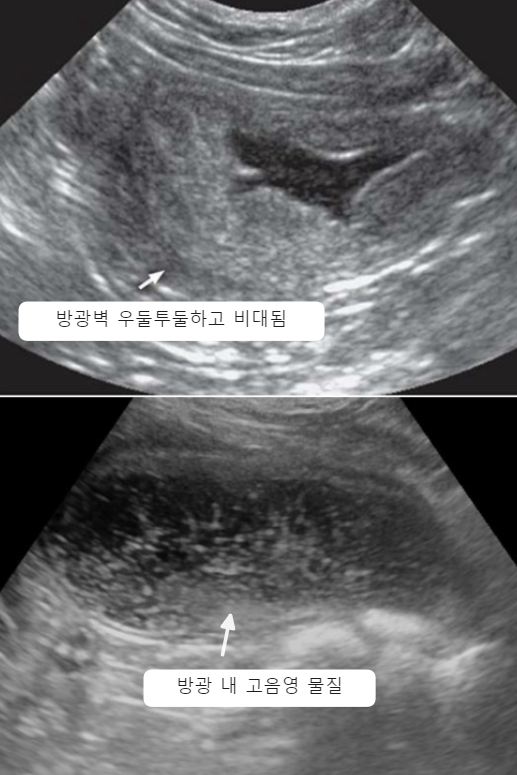

| Ultrasonography (Abd) _Cystitis | |

![]() | - ๋ฐฉ๊ด๋ฒฝ ๋นํ, ์ฐ๋ํฌ๋(โต์ข

์, polyp) - ๋ฐฉ๊ด ๋ด๊ฐ์ Echogenic sediment ![]() + Cystocopy(๋ฐฉ๊ด๋ด์๊ฒฝ) : ์๋ โ ๋ฐฉ๊ด ๋ด๋ถ ๊ฐ์ผ ํ๋ฅ ์กด์ฌ |